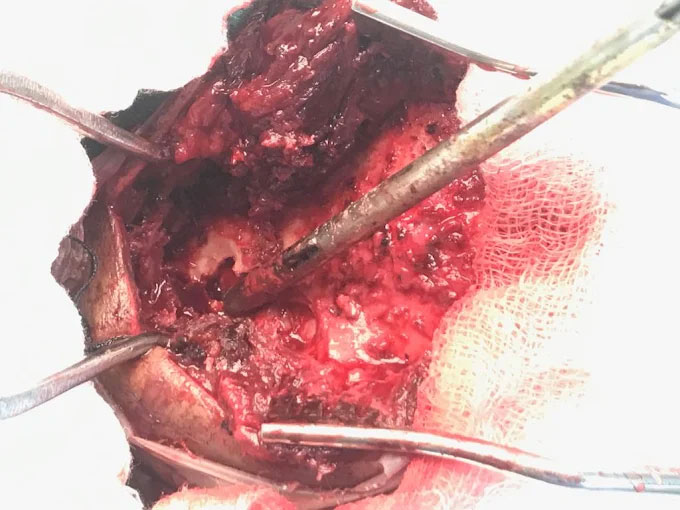

Dr. Ujwal Yeole is an experienced neurosurgeon specializes in treating a wide spectrum of neurological conditions including neuro-oncology, peripheral nerve disorders, vascular disorders, spinal pathologies, pediatric neurosurgery, neuro-trauma and skull base neuroendoscopic procedures.